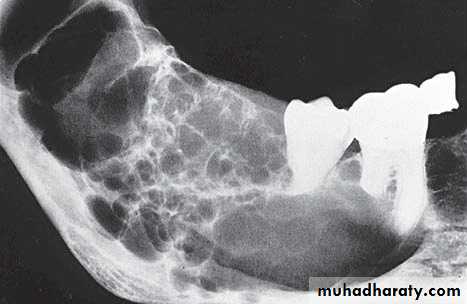

• Aneurysmal Bone Cyst

Large multilocular aneurysmal bone cyst

in the ramus with marked expansion andthe displacement of/8.

It is non-neoplastic ,exaggerated , localized, proliferative lesion of vascular tissue, containing giant cells.

It’s a variation of the central giant cell granuloma , can be diagnosed only by histological examination